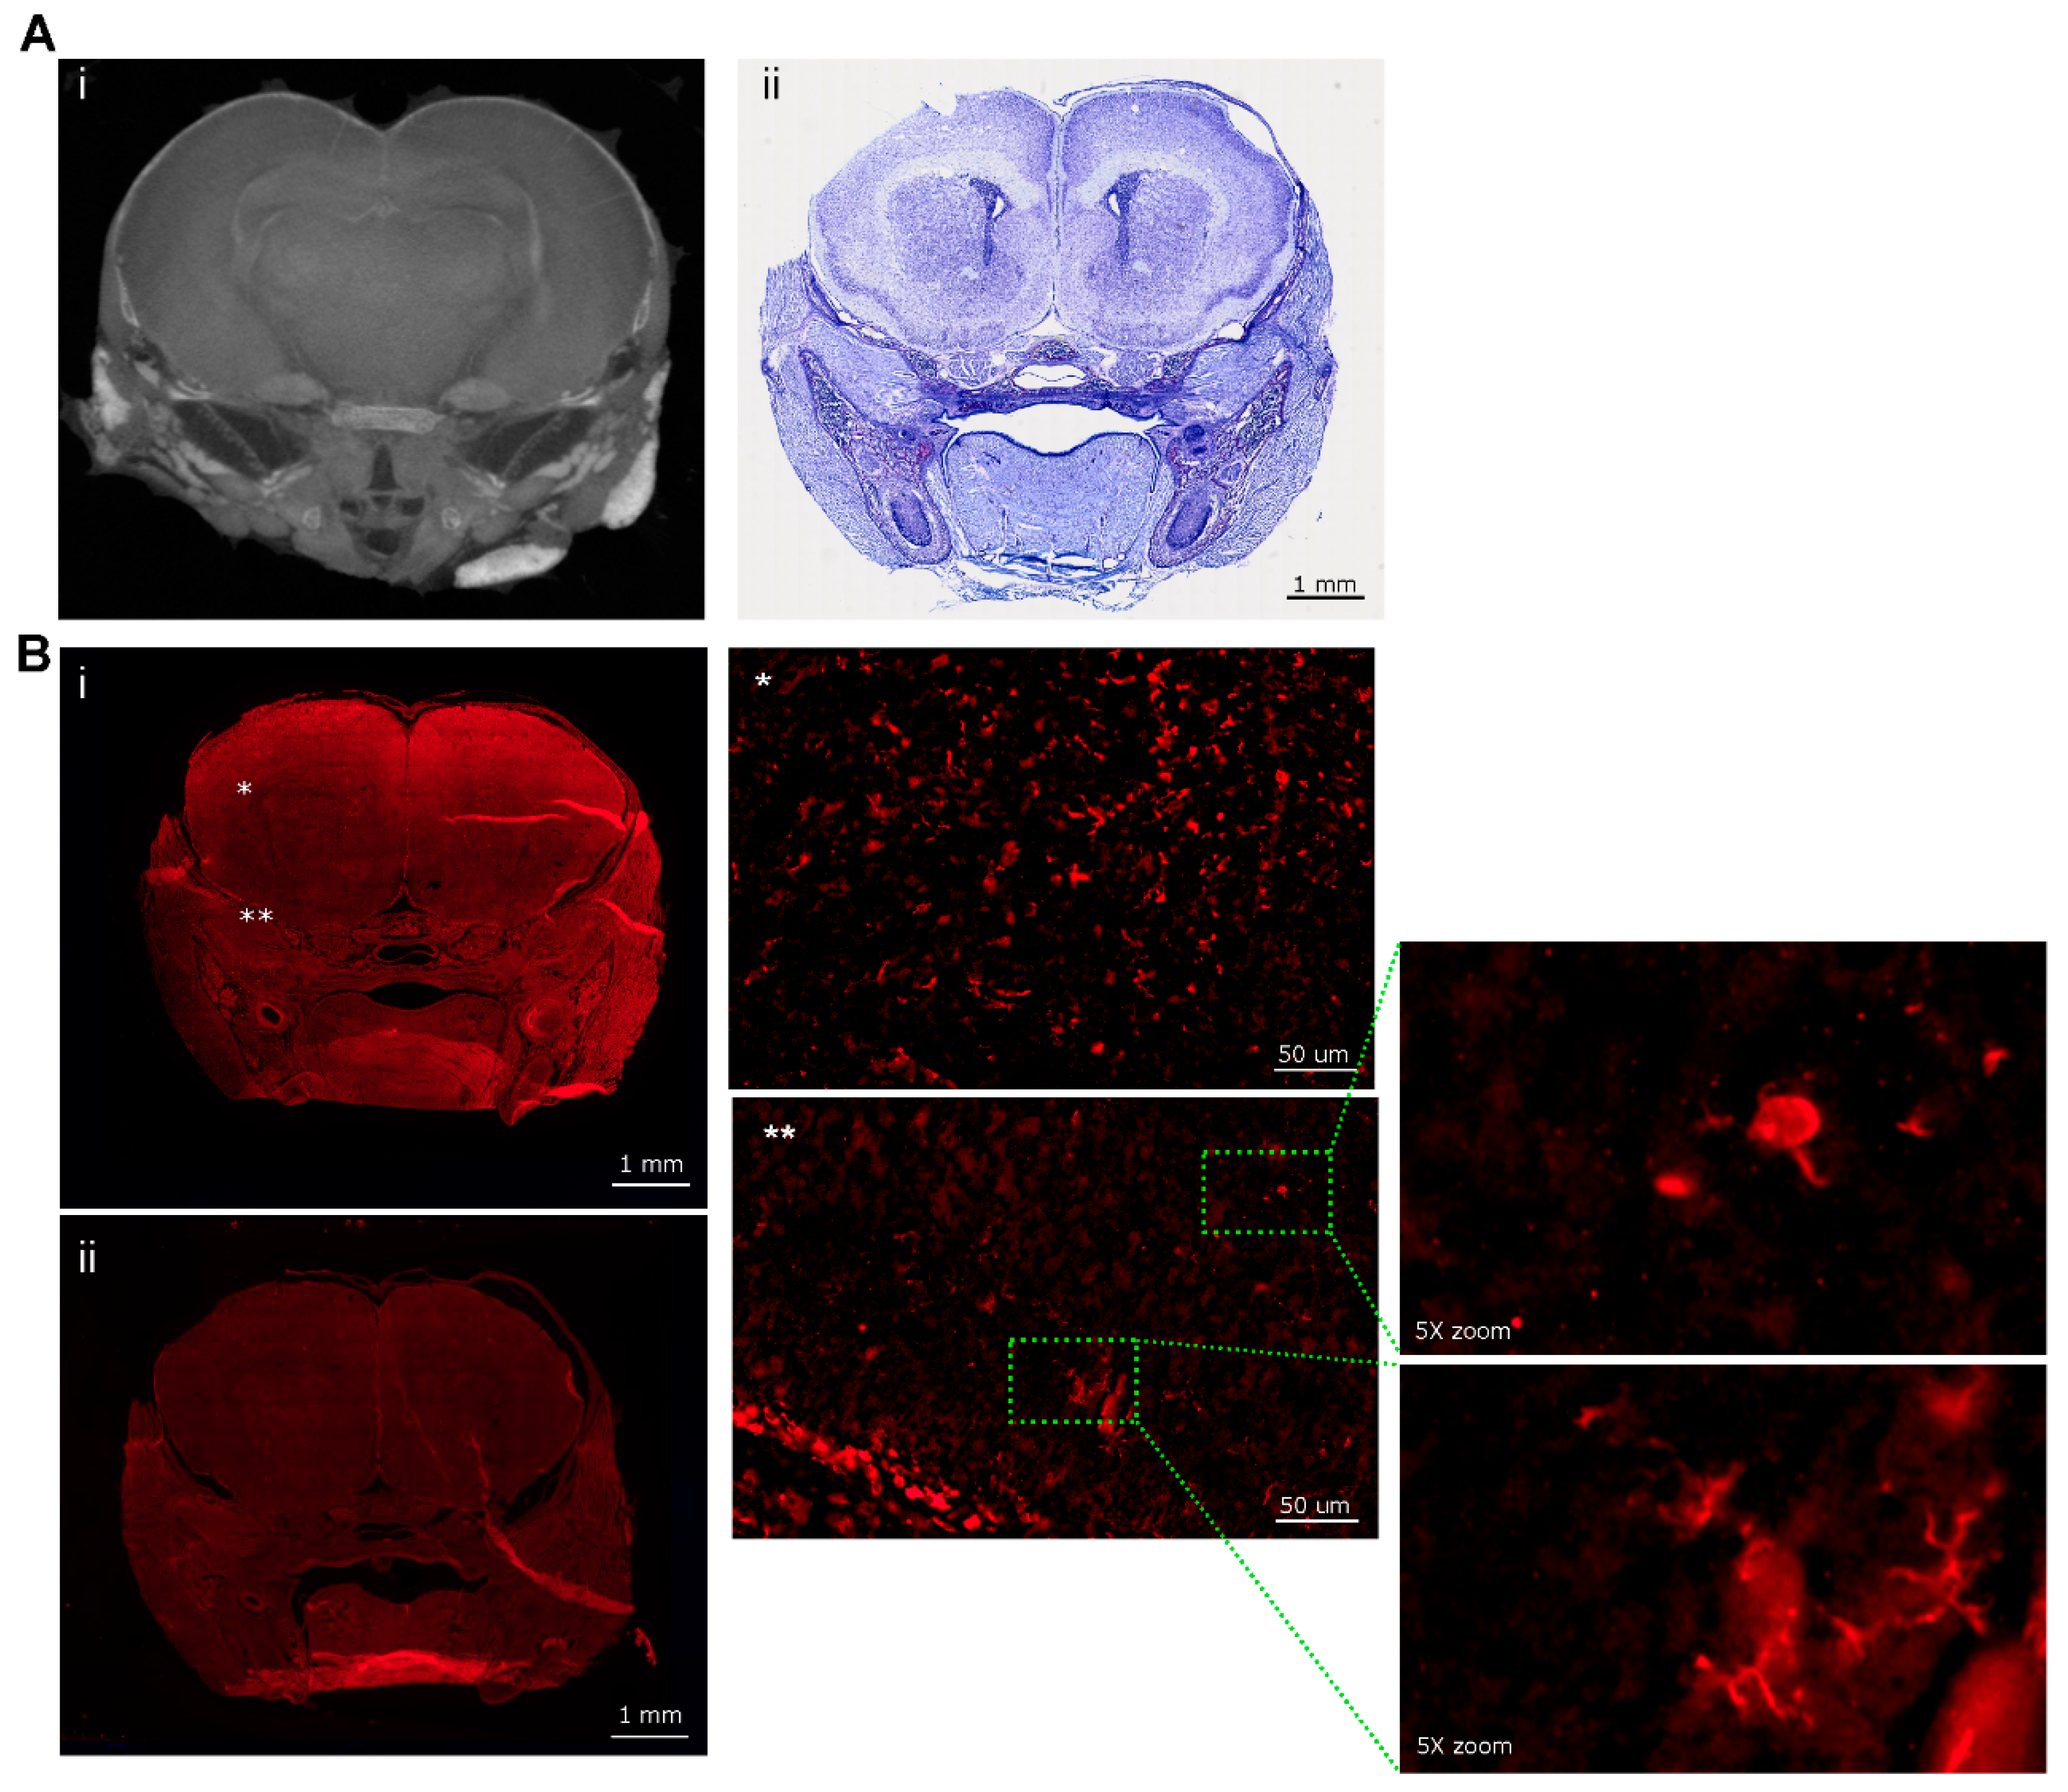

- Gignac, P.M.; O’Brien, H.D.; Sanchez, J.; Vazquez-Sanroman, D. Multiscale imaging of the rat brain using an integrated diceCT and histology workflow. Brain Struct Funct 2021, 226, 2153–2168. [Google Scholar] [CrossRef]